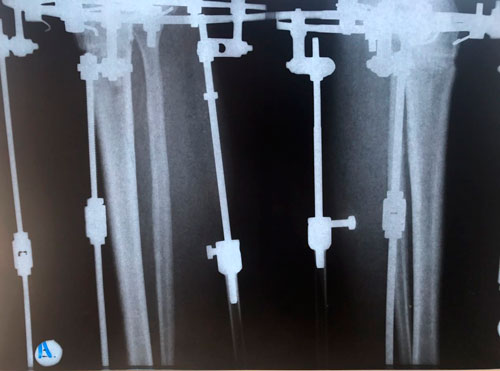

Дата операции 21.03.2018г.

Дата снятия аппаратов 06.07.2018г.

Срок лечения 105 дней.